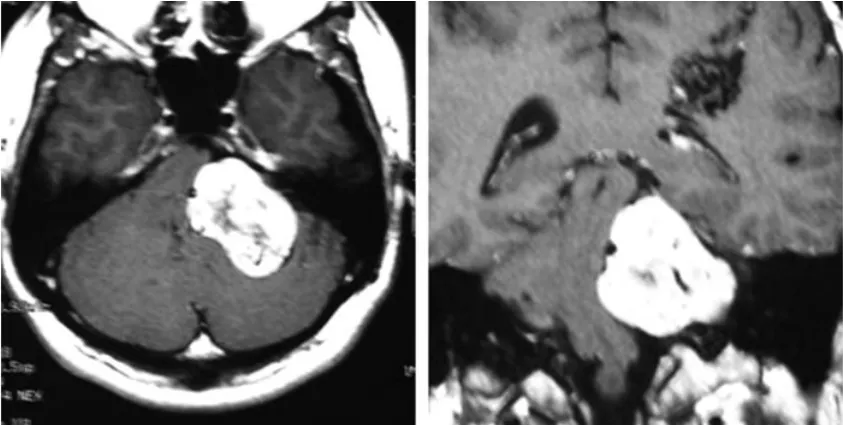

这名27岁男性最初因左侧面部麻木和平衡功能下降前来就诊。影像学检查显示,其左侧桥小脑角区存在一处直径约4.5厘米的占位性病变,影像特征与听神经瘤高度吻合,且肿瘤体积已对脑干造成明显压迫。

面对体积较大的肿瘤,治疗团队制定了手术切除联合放射外科的阶梯化治疗方案。患者首先接受了左侧听神经瘤的部分切除手术。术中由于合并动静脉畸形导致静脉压持续升高,止血操作极为困难,肿瘤未能实现全切。手术结束后,针对残余病灶采用伽玛刀立体定向放射外科治疗,处方剂量15 Gy,脑干区域受量严格控制在9 Gy以内。术后六个月,患者再次接受伽玛刀治疗,这一次针对的是顶叶深部的动静脉畸形。

初次治疗结束后两年,患者因症状再次出现而复诊,影像学检查提示肿瘤体积有所增大。随即安排第二次手术切除,术后病理报告显示仍为良性前庭神经鞘瘤,未发现任何恶性转化的组织学依据。